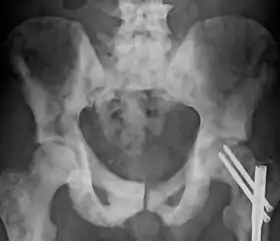

Остеосклероз — патологічний стан, підвищення кісткової щільності, що виявляється у вигляді потовщення кісткових трабекул і компактної речовини кістки. Губчаста кістка за остеосклерозу набуває вузькопетлистої структури. У зв'язку з тим, що ущільнена кісткова тканина стає менш прозорою для рентгенівських променів, остеосклероз можна діагностувати рентгенологічними методами досліджень. Розрізняють фізіологічний остеосклероз (відзначається в процесі росту скелета в області росткових зон) та патологічний остеосклероз.[1] У числі захворювань, що супроводжують остеосклероз — мелореостоз, остеопетроз, остеопойкілоз, хронічний ідеопатичний мієлофіброз тощо. Субхондральний остеосклероз є одним із проявів остеоартрозу.